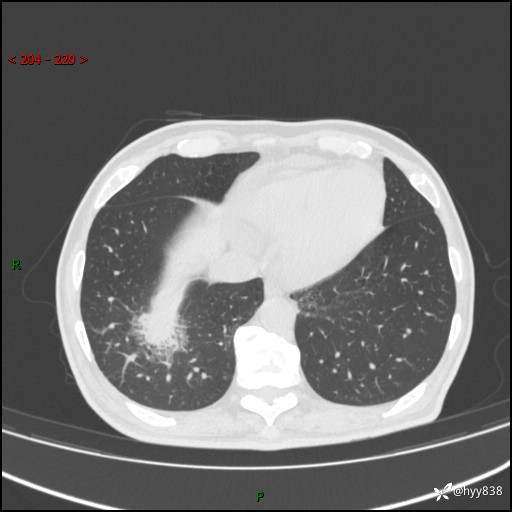

66岁/男,确诊髓系白血病5月,乏力伴气促半月。孤立结节,“晕”的厉害---结果公布~

【患者信息】:66岁/男

【主诉】:确诊髓系白血病5月余,乏力纳差伴气促半月

【现病史及既往史】:患者5月前无明显诱因出现牙龈出血,未重视,2024.5.10社区体检查血常规发现全血细胞减少,后自觉活动后心慌气促,无发热、头痛、咳嗽咳痰、胸痛等,为进一步诊治来我院,门诊以“全血细胞减少”收入,入院后完善相关辅检入院后确诊急性髓系白血病。于2024.06.11给予阿扎胞苷+维奈克拉化疗,给予输血、升白细胞、抗过敏、止血治疗,化疗后粒细胞缺乏,转入层流病房,出现发热,予以抗感染(头孢唑肟、莫西沙星、美罗培南)、抗真菌(卡泊芬净、氟康唑)、利尿、调脂、利胆、护心、护胃、调节免疫(羟氯喹、白芍总苷)、通便、调节胃肠道菌群、营养支持等对症治疗,出院时患者牙龈出血、咳嗽咳痰、腹胀、便秘等不适较前好转,复查血常规提示白细胞计数升高,要求出院,建议继续住院观察,但患者仍要求出院,予以办理。2024-08-06到我院规律化疗,2024-08-08给予阿扎胞苷+维奈克拉化疗,给予输血、升白细胞、抗过敏、止血治疗,化疗后粒细胞缺乏,转入层流病房,出现发热,予以护心、护胃 、营养支持等对症治疗,好转后出院。院外自行停用维纳克拉。半月前患者无明显诱因出现乏力、纳差、活动后气促,无心慌、胸闷,无咳嗽、咳痰,无畏寒、发热等不适,现患者为求进一步诊治来我院,门诊以“急性髓系白血病”收入院。 发病以来,患者精神、饮食欠佳,睡眠一般,大小便如常,体力明显下降,体重无明显减轻。

【检查】:胸部CT平扫